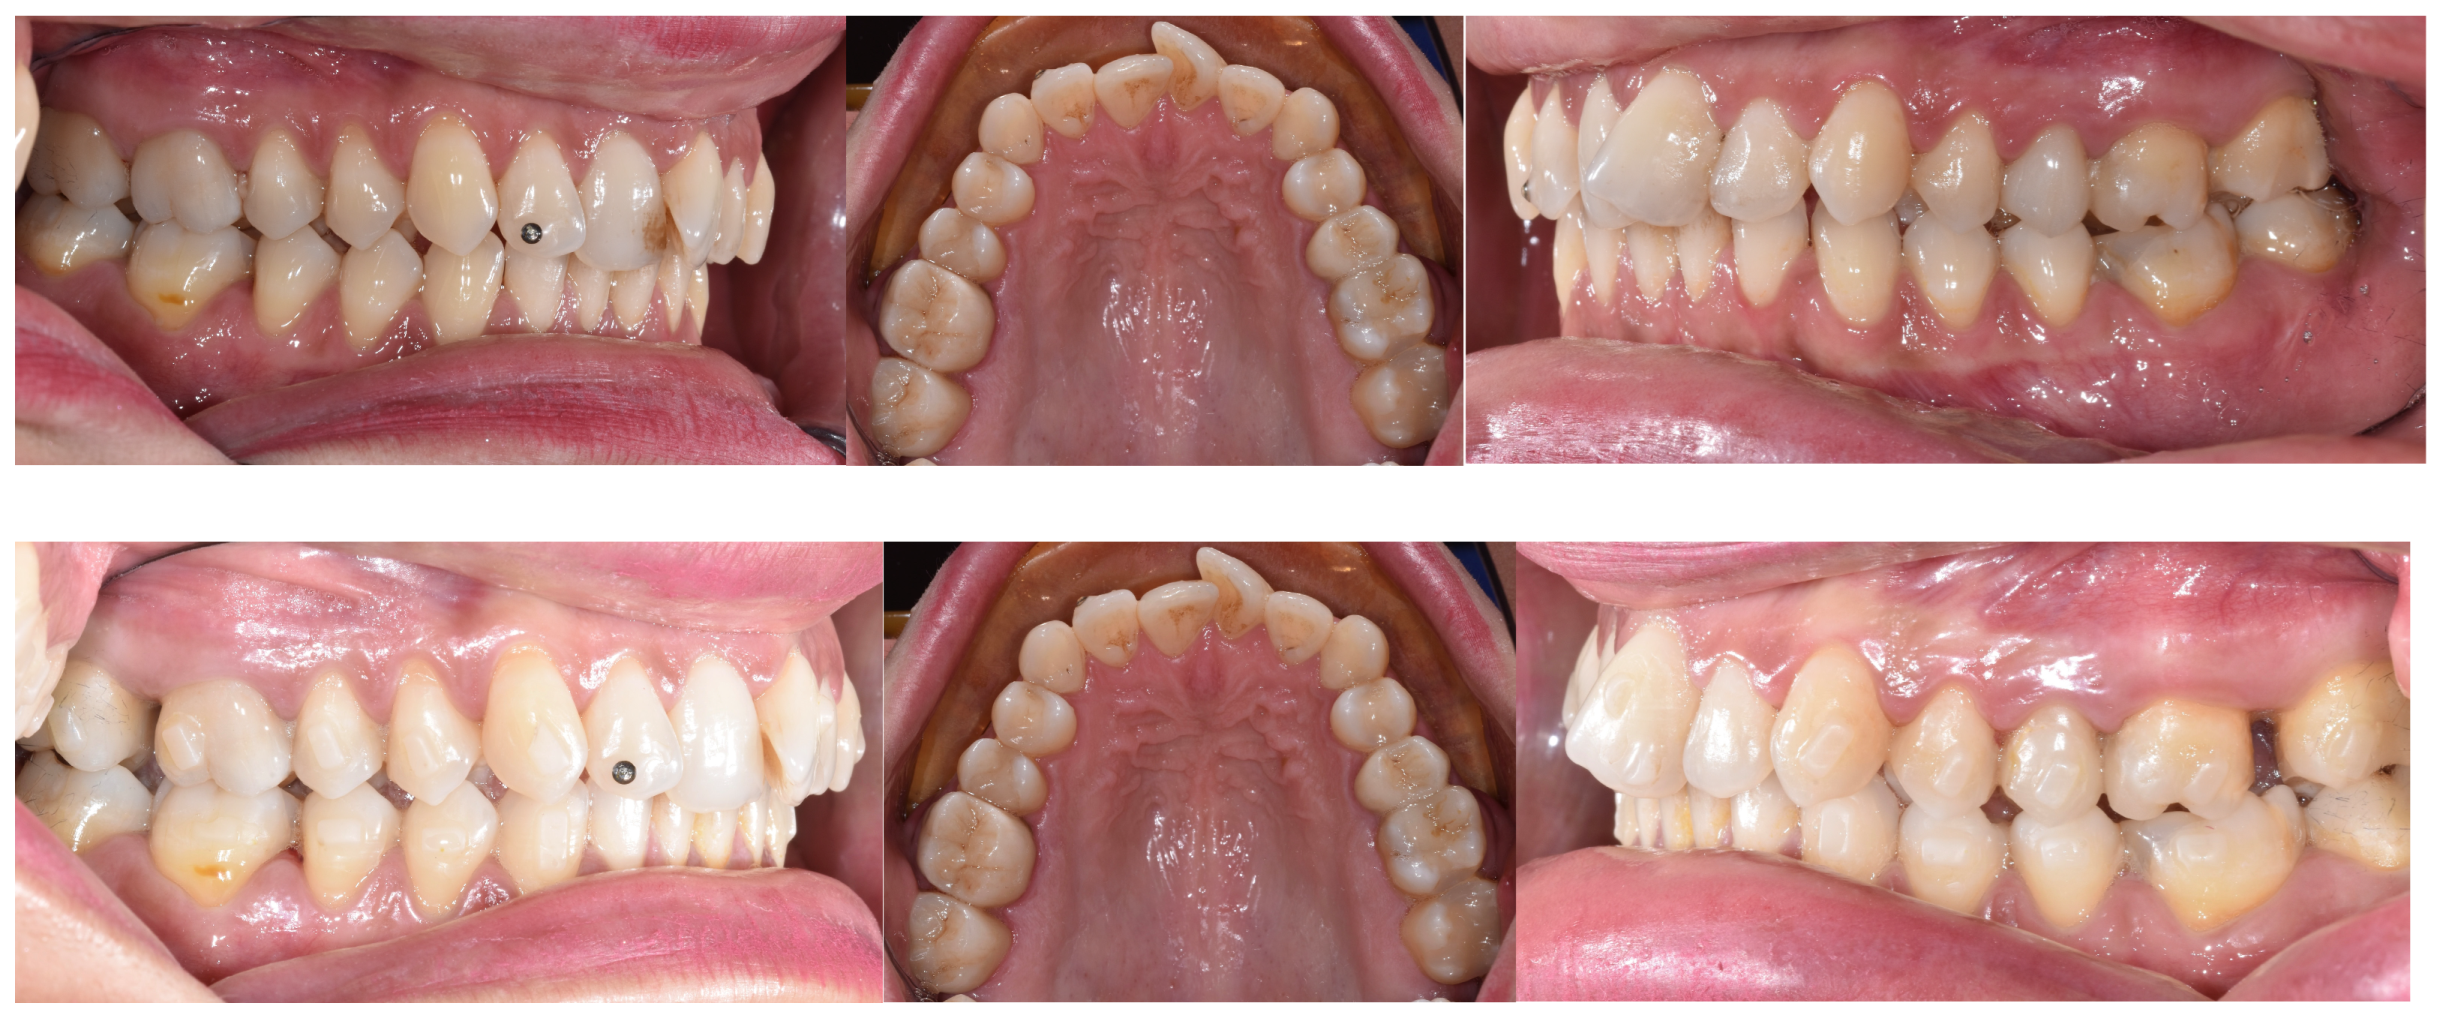

- Staderini, E.; Ventura, V.; Meuli, S.; Maltagliati, L.Á.; Gallenzi, P. Analysis of the Changes in Occlusal Plane Inclination in a Class II Deep Bite “Teen” Patient Treated with Clear Aligners: A Case Report. Int. J. Environ. Res. Public Health 2022, 19, 651. [Google Scholar] [CrossRef] [PubMed]

- Lu, W.; Li, Y.; Mei, L.; Li, Y. Preformed Intrusion Bulbs on Clear Aligners Facilitate Active Vertical Control in a Hyperdivergent Skeletal Class II Case with Extraction: A Case Report with 4-Year Follow-Up. APOS-Trends Orthod. 2023, 13, 46–54. [Google Scholar] [CrossRef]